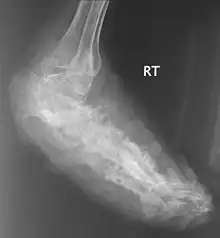

Eumycetoma, also known as Madura foot,[1][6] is a persistent fungal infection of the skin and the tissues just under the skin, affecting most commonly the feet, although it can occur in hands and other body parts.[5] It starts as a painless wet nodule, which may be present for years before ulceration, swelling, grainy discharge and weeping from sinuses and fistulae, followed by bone deformity.[3]

| An infected foot | |

X rays and ultrasonography may be carried out to assess the extent of the disease. X rays findings are extremely variable. The disease is most often observed at an advanced stage that exhibits extensive destruction of all bones of the foot. Rarely, a single lesion may be seen in the tibia where the picture is identical with chronic osteomyelitis. Cytology of fine needle aspirate or pus from the lesion, and tissue biopsy may be undertaken sometimes.[11] Some publications have claimed a "dot in a circle sign" as a characteristic MRI feature for this condition (this feature has also been described on ultrasound).[14]